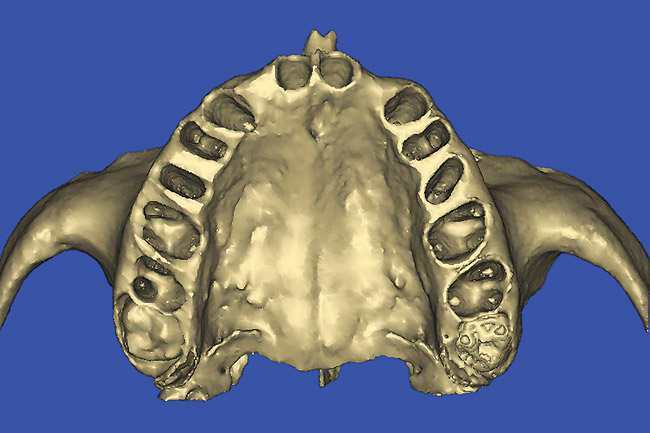

Figure 12  SOFTWARE IMAGING The 3D reconstruction showed the facial concavities and root eminences.

Figure 12

After the basic plan had been established, it was re-evaluated using interactive 3D images. The reconstructed 3D view of the maxilla clearly illustrated the extent of the bilateral facial concavities, and the root eminences of the adjacent and posterior teeth (Figure 12). The placement of the virtual implants then was evaluated to ensure that the facial cortical plate was not perforated (Figure 13). The implants were labeled individually as “7” and “10,” with the simulated yellow abutment projection indicating the facial-lingual inclination through the bone to the level above the incisal edge of adjacent teeth. The ability to gain a better understanding of these individual root forms cannot be underestimated. The dental literature has suggested certain parameters for placing implants near teeth and implants next to other implants. However, there is little scientific 3D documentation to support these suggested rules.5-10 The use of an interactive treatment-planning software application permits closer scrutiny of previously difficult-to-visualize areas, and can now be used to redefine perceptions of spatial positioning of implants, especially when in close proximity to natural tooth roots, vital anatomy, and adjacent implants.27-29

Using different masking (segmentation) and threshold Hounsfield unit values, several new 3D bone volumes can be created which offer invaluable information. To help determine the final position of each implant a new bone model was created with a Hounsfield unit value of 1480, which eliminated all but the densest objects included in the scan data. (Results may vary depending on the CBCT machine used.) The inner and outer layers of bone were removed, leaving the underlying enamel and root structure of the teeth (Figure 14). After the bone had been stripped away, the root inclinations were examined closely. The most striking findings confirmed the rotated position of the right central, while revealing the slight mesial dilaceration of the root apex, which converged on the space needed for the path of the potential implant (Figure 15). The schematic shapes of the proposed implants were visualized for the right and left lateral spaces in different rotations of the 3D maxillary arch. It was at this point that a determination was made as to the appropriate implant shape and type that would fit the available space while avoiding encroachment on adjacent tooth roots. A tapered design implant (Tapered Screw-Vent®, Zimmer Dental, www.zimmerdental.com) was chosen from the large virtual library. With the SIMPlant software, the virtual library contains data from dozens of implant manufacturers and realistic computer-aided design representations as seen in Figure 16 through the translucent bone. The position of the left implant can be visualized with adequate mesial-distal distance between adjacent tooth roots (Figure 17) and a more delicate placement (Figure 18).